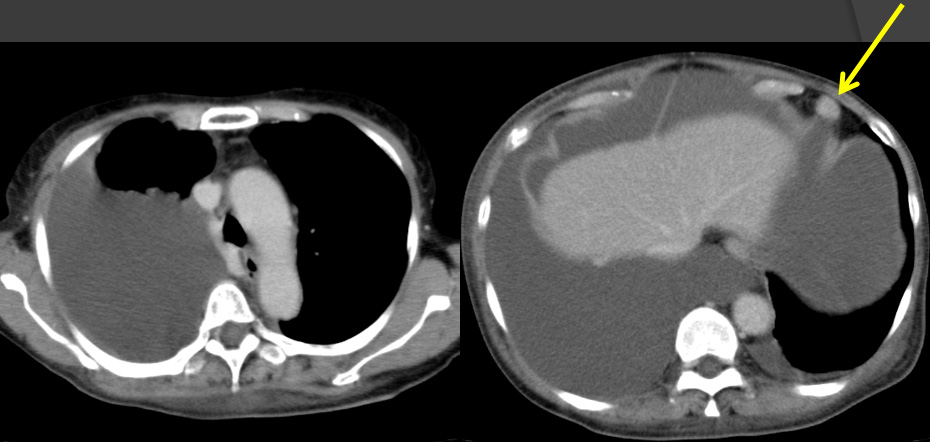

Dedifferentiated solitary fibrous tumor (SFT) in the pelvis

術後5カ月 手術+化学療法後再発

胸膜、腹腔内、腹膜に播種性に再発